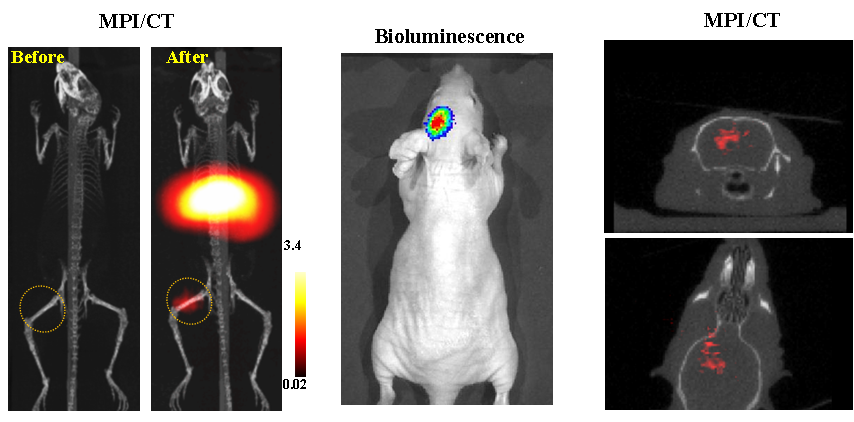

今年二月份,宋国胜教授与斯坦福大学饶江宏教授合作,通过系统的研究获得了影响磁性粒子成像信号的作用规律和关键原理,开发了新型磁性粒子探针---FeCo合金粒子,并首次应用于磁性粒子成像(MPI)。该造影剂在极低含量时(5 ng)仍具有很强的造影效果。这意味着,未来在进行人体成像时,可以使用更小剂量的造影剂,从而避免高剂量造影剂引起的肾肝损伤。基于MPI的直接成像原理,我们可以对造影剂进行正相和无背景干扰的活体成像,极大地提高信噪比。这项技术为肿瘤早期诊断、癌细胞示踪、脑中风、药物输送治疗、肺部灌注成像、胃肠出血、神经退行性疾病、磁热治疗等在活体中的可视化研究,提供了强有力的手段。相关研究成果以抢庄牛牛官方网站

为第一单位发表在Nature 子刊《Nature Biomedical Engineering》。该期刊是“生物医学工程”的顶级期刊。宋国胜教授为该论文的共同通讯作者。